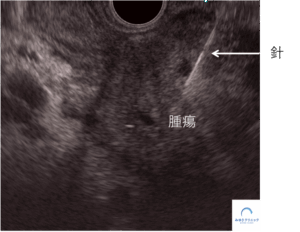

腫瘍の確定診断のために、超音波内視鏡ガイド下穿刺診をおこない、大学病院を受診していただく手配をしました(ここまでで、初診からわずか2日間です)。

<超音波内視鏡ガイド下穿刺診>

後日、細胞診で膵がんの診断がつきました。